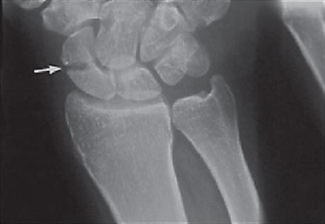

- Positivt fund på røntgen eller MR